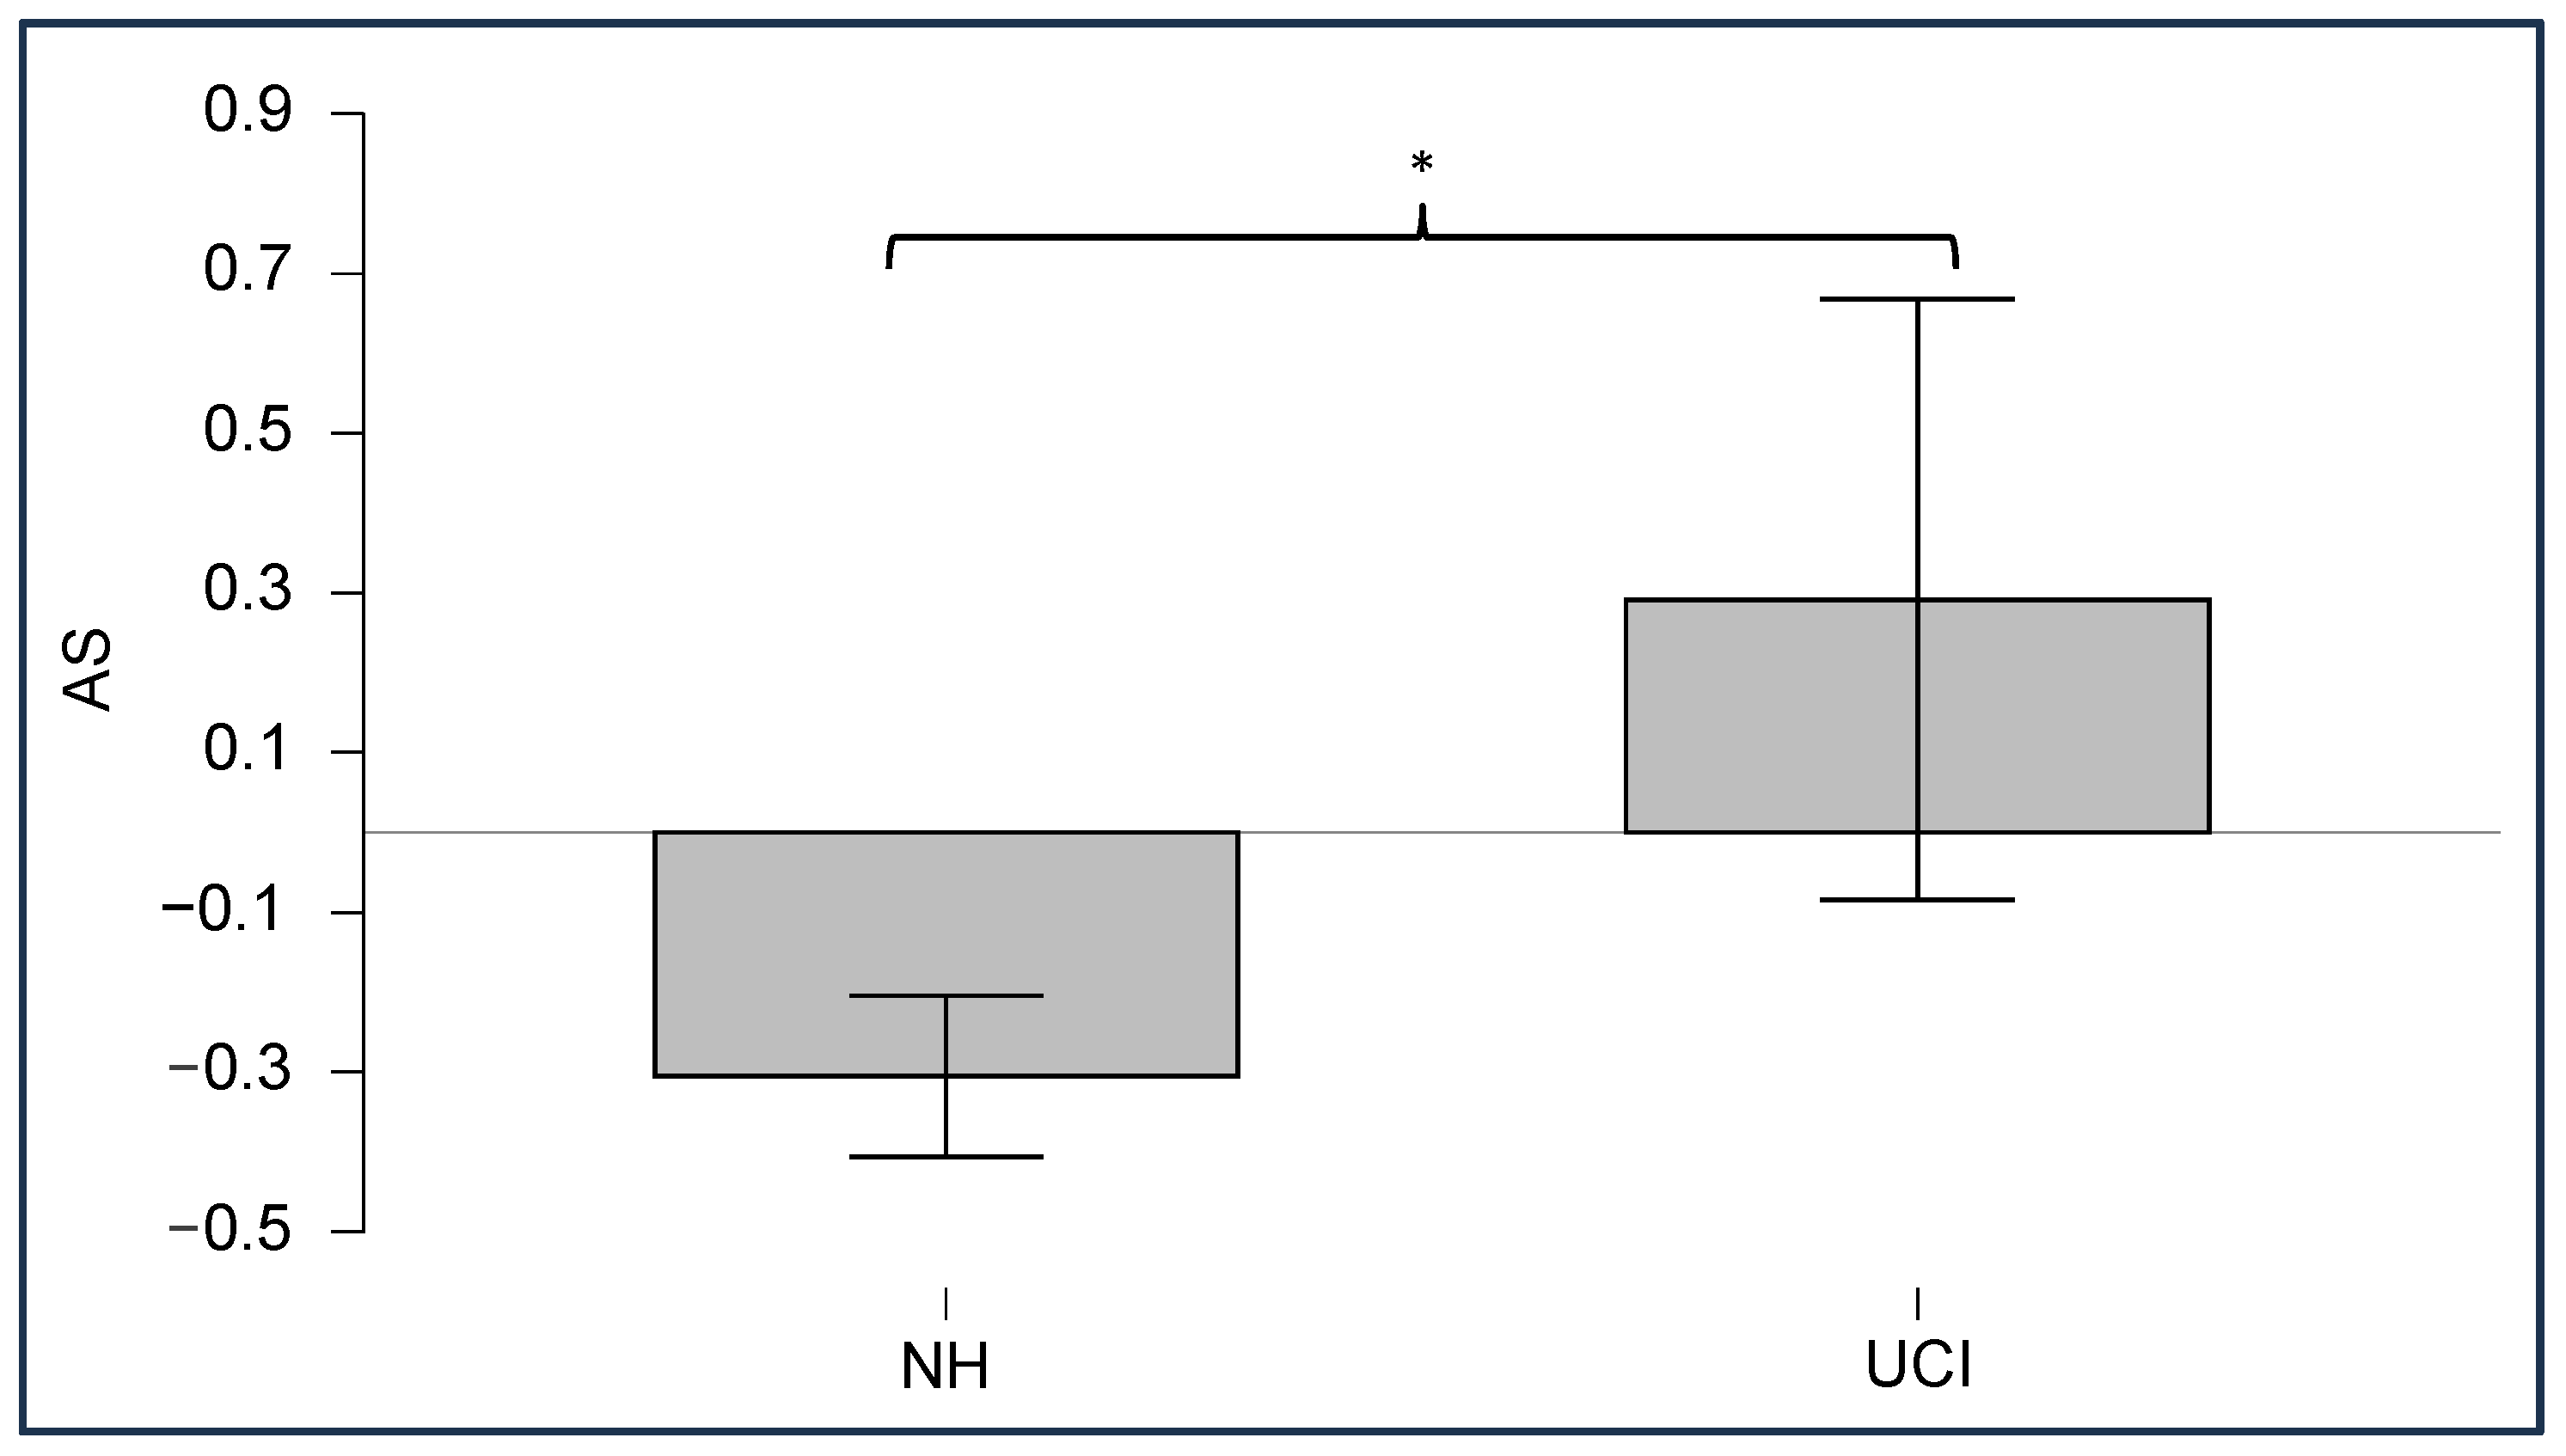

3.2. CI Artifact Reduction

3.3. Neurophysiological Results